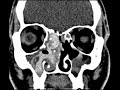

Allergic Fungal Sinusitis

These images demonstrate serpiginous centrally hyperdense material completely opacifying the right maxillary sinus, right ethmoid air cells, and portions of the right nasal cavity. There is associated osteitis of the posterior right maxillary sinus wall and erosions of the right ethmoid air cells. There is less involvement of the left maxillary sinus and left ethmoid air cells where post-surgical changes are noted. Findings are compatible with allergic fungal sinusitis. This is thought to occur as a result of an allergic response in immunocompetent patients to aerosolized fungi and hyperdense areas do not represent fungus itself. Usually multiple sinuses are involved with central hyperdense material and osseous erosions. Treatment may include surgical excision and steroid therapy.